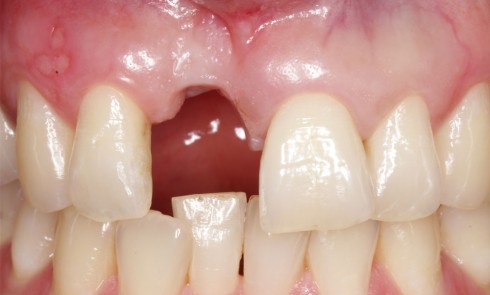

Article réservé à nos abonnés L’implantologie en secteur esthétique : importance du contexte parodontal

De nombreuses études ont montré que la stabilité dans le temps des tissus mous péri-implantaires est primordiale et conditionnée par...